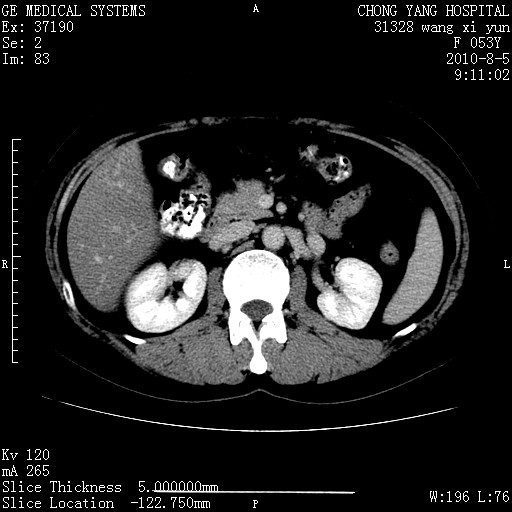

标题: CT28214:F41Y 血尿二十天,建议盆腔平扫加增强。

胆管细胞ca?

1)考虑肝左叶胆管细胞癌。2)脂肪肝。

支持胆管细胞ca。